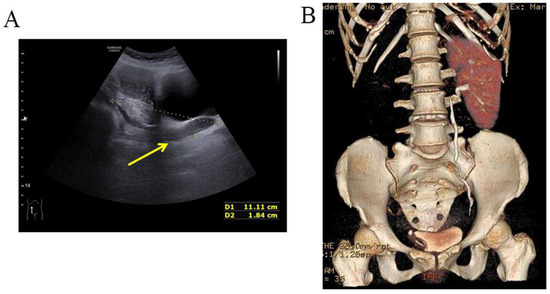

A woman of 33 years old was advised to undergo a hysteroscopy before receiving assisted reproductive technologies. She received a hysteroscopic uterine septum resection at age 27. Her right fallopian tube was removed due to two ectopic pregnancies. A pelvic examination showed an oblique septum extending 3 cm from the left fornix of the vagina to the hymen border. The pelvic ultrasound demonstrated an ectopic ureter or ureterovaginal fistula (Figure 10). An MRI and CTU detected left renal agenesis and a left dilated ureter with an ectopic opening. Following vaginal septum excision, a double cervix with a dysplastic left cervix was found. Given that the left ectopic ureter was asymptomatic, this ectopic ureter was not surgically removed.

Figure 10.

The pelvic ultrasound demonstrated that a sausage-shaped ectopic ureter (yellow arrow) was found behind the uterus and bladder.